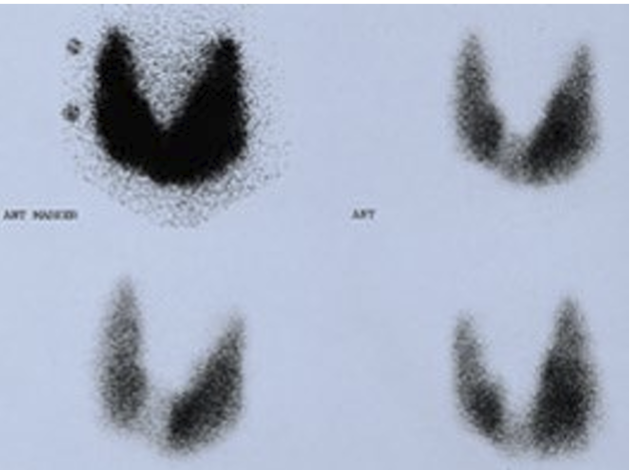

What does this show in what disease

Enhanced RAIU, hyperthyroiditis → Graves Disease

Decreased RAIU, hypothyroiditis → Hashimoto thyroiditis